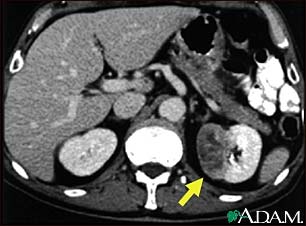

Kidney tumor - CT scan

This CT scan of the abdomen shows a tumor in the left kidney (called hypernephroma, or renal cell carcinoma). It is located on the lower right side of the picture.